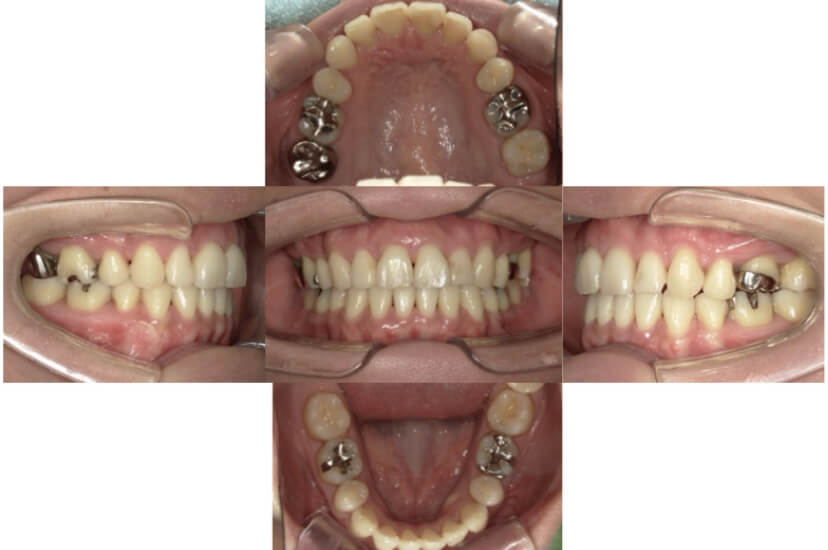

症例2

上下顎前突、叢生

抜歯

ブラケット矯正

上下顎前突、叢生(上下出っ歯、上下の前歯のガタガタ)のケースです。

装置はラビアル(上下表側)で、上下顎の小臼歯を4本抜歯を行っています。抜歯したスペースを使って、上下の前歯の後方移動と叢生(ガタガタ)の改善を行っています。

主訴 前歯のガタガタと口元がでているのが気になる。

年齢・性別 30歳 女性

お住まいの地域 東京都大田区

治療方針 抜歯スペースを利用して上前歯の叢生(ガタガタ)と口元突出の改善

抜歯部位 上下顎左右第一小臼歯

使用装置 ラビアル(上下表側)、顎間ゴム

治療期間 1年11か月

治療回数 13回

リテーナー クリアリテーナー

BEFORE

AFTER